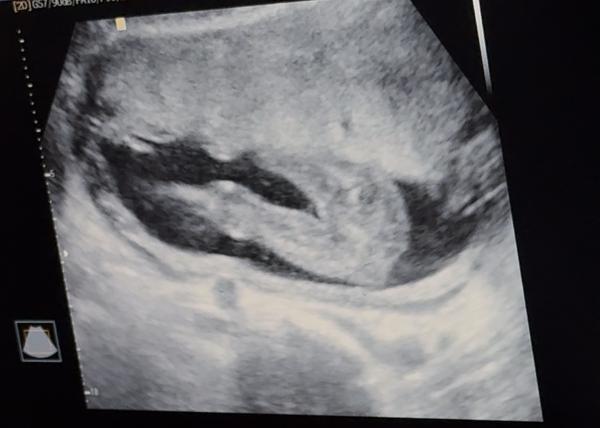

My se snažili o miminko 3 roky, dvakrát IUI a 1x IVF se 3 vklady a za tu dlouhou dobu jen jednou biochemické. Teď se jako zázrakem zadarilo po laznich přirozeně a jsem 6tt + 5 cca. Nicméně k minulým zkušenostem mám obavy a ráda bych si s někým psala a uklidnila se, jelikož ve svém okolí nemám nikoho, kdo by na tom byl teď podobně jako já a kromě manžela to nemám moc s kým sdílet.

@puraniani my jsme se snazili 6 let.. pred dvema lety jedno biochemicke 🙏 premlouvala jsem pritele porad na ivf jednou jsme tam uz i sedeli ale on to hrozne nechtel casto jsme se kvuli toho dohadovali.. rikala jsem si ze uz dite nebude.. ted jsme jeli koncem srpna na dovcu a prijela jsem 2 v 1 😻🩷 byla jsem na kontrole 5+6 trosku jsem si tu kontrolu vynutila 😁 a uz bylo videt i srdicko ted jsem 6+2 a doufam ze vse bude v poradku 🩷 strach je porad ale rikam si ze co se ma stat se stane a nebudu myslet na spatne veci nekdy to nejde ale stejne nic neovlinim 🍀 takze drzim pesti vsem 😻